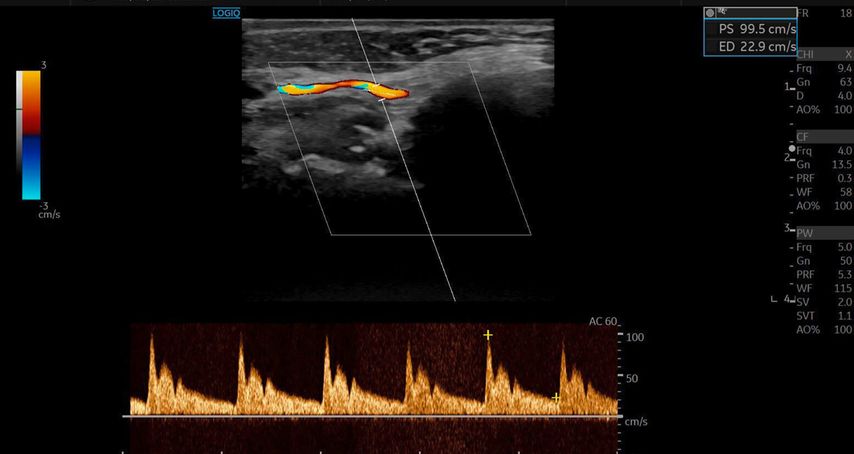

Die A. facialis imponierte beim Austritt im Bereich des Musculus masseter (oberhalb der Kieferlinie) vasospastisch mit einem maximalen Durchmesser von 1mm. Die abgeleitete systolische Spitzengeschwindigkeit betrug trotz der bestehenden Ischämie 20cm/s, ohne enddiastolische Komponente, was auf eine weitere periphere Vasokonstriktion hindeutete (Abb. 2 und 3).

Die A. facialis ist die Hauptarterie zur Blutversorgung des Gesichts und entspringt aus der A. carotis externa. Sie hat einen stark geschlängelten Verlauf und bildet zahlreiche Anastomosen mit benachbarten Arterien. Ihr Durchmesser variiert entlang ihres Verlaufs: Am Unterkieferrand liegt der mittlere Durchmesser bei 2,4mm, in der Wangenregion bei 1,9mm und im Bereich der Nasolabialfalte bei etwa 1,5mm. Die A. angularis, der Endast der A. facialis, weist einen Durchmesser von ca. 1,2mm auf. Die Flussgeschwindigkeit variiert je nach Region, beträgt aber durchschnittlich zwischen 20–50cm/s.1

Sonografisch lässt sich die A. facialis am besten an der Vorderseite des Musculus masseter detektieren. Sie zeigt eine deutliche Pulsation, und ihre Hauptäste – A. labialis inferior, A. labialis superior und A. angularis – sind aufgrund ihrer oberflächlichen Lage gut darstellbar.